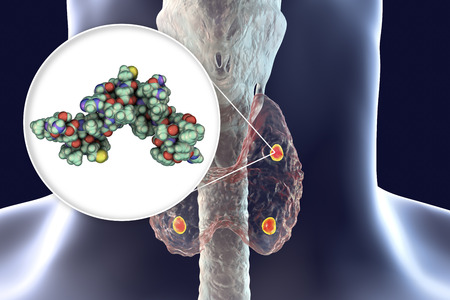

Molecular model of antibody taking part in immune defense. Molecule of immunoglobulin, 3D illustration

Human parathyroid hormone, molecular model, 3D illustration. Also called parathormone, parathyrin, is secreted by the parathyroid glands and takes part in bone remodeling